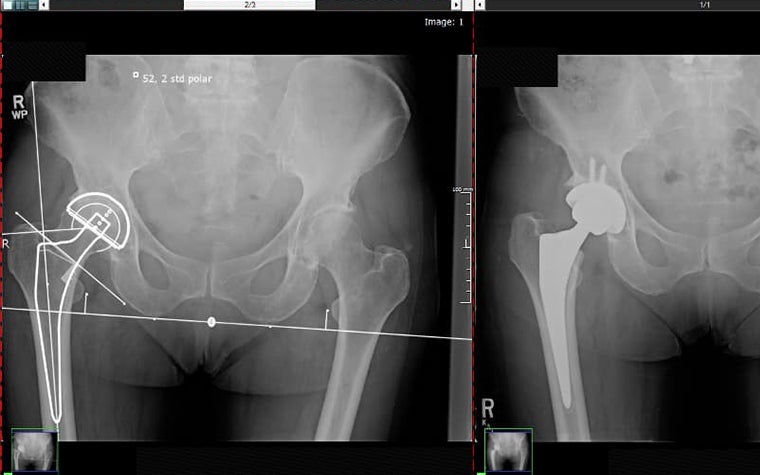

Preoperative planning plays an essential role in the successful outcome of joint replacement surgery. It helps doctors achieve optimum mobility and a pain-free life for their patients. Digital planning software makes it easier for orthopaedic surgeons to confidently predict the right implant size and position before going into the OR.

Since transitioning to digital preoperative planning, Dr. Noble now finds that he relies on his templated images even more in the OR, particularly for judging the level of resection, alignment, sizing, and leg length.

Dr. Noble found another unexpected benefit of digital orthopaedic templating over analog with printed X-rays and acetate templates. Digital pre-planning has led to better team collaboration, ultimately reducing time spent in surgery: “Digital templating not only prepares me as the surgeon, but also the surgical tech, for each case. The surgical techs review my templates just prior to our case, allowing them to prepare the back-table with the appropriate instruments and trials based on the components and sizes that I have templated. This allows the case to flow more efficiently, thereby reducing OR time."

Dr. Noble now plans all of his hip and knee cases digitally, and he says, “I feel more confident with my pre-surgical plan and surgical outcomes now that I plan all my procedures digitally. I know that I will have the correct prosthesis for the patient's anatomy since I templated the case in advance.”